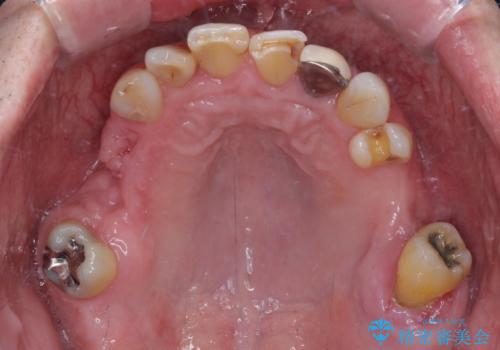

欠損の多い奥歯 インプラントによる補綴治療

- 地元ではなかなかインプラント治療を行ってくださる医院がないとのことで、転勤で東京にいる期間に治療を行いたいとのことで来院された患者様です。

上顎は左右ともに骨が少ない状態であり、特殊なドリルを用いた歯槽骨の拡大や自家骨挙上などを行いながらインプラントを埋入していくこととしました。

右下の銀歯も気になるとのことで、インプラント治療と並行してオールセラミックによるブリッジ補綴治療も行うこととしました。